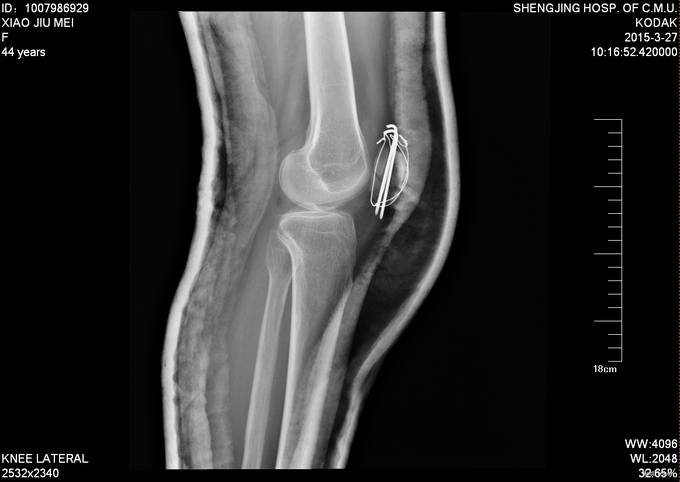

主诉:摔伤后左膝部疼痛肿胀活动受限4小时 患者及家属述患者于2015-3-14日9点40于自家不慎摔倒,导致左膝部疼痛肿胀活动受限,家人急送至沈阳市骨科医院,行DR检查示:左髌骨骨折。未行任何处理,现患者为求进一步诊治来我院,急诊以“左髌骨骨折”为主要诊断收入我科。患者自受伤以来,无发热,无呼吸困难,饮食睡眠正常,二便正常。

专科查体:患者平车入病房,。左膝部肿胀明显,压痛(+),活动受限。双下肢感觉正常 ,足趾活动可,足背动脉可触及。

诊断:左髌骨骨折 患者入院后见患肢肿胀明显,给予患肢石膏固定抬高位,冷敷,甘露醇消肿等对症治疗,带患肢出现褶皱试验阳性后,CSEA下行左髌骨骨折切口复位张力带内固定术,术后患者肿胀明显,给予,消肿,冷敷,患肢抬高等对症治疗。患者每天换药观察切口愈合情况,无红肿及渗出,待伤口12天后予以拆线治疗,予以出院,给予康复处方。